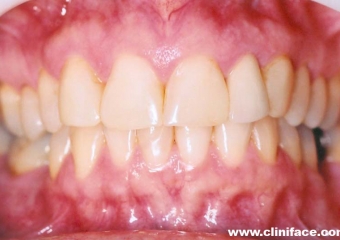

Imagem inicial e final de caso de agenesia dental, reabilitado com implante unitário no elemento 12

Prótese fixa sobre implante, finalizado em janeiro de 2010